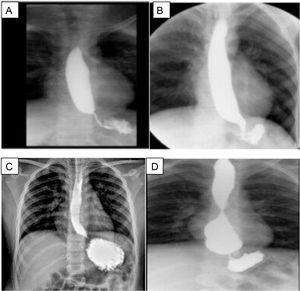

The four patients presented with dysphagia after the surgical procedure, at a mean of 2 weeks (2 ± 1.2 weeks). Therefore, the first diagnostic test carried out was an esophagram, which revealed stricture of the esophagogastric junction (EGJ) in all four cases (Fig. 2A-D). The patients then underwent endoscopy. In two patients, passage of the endoscope was difficult, there was angulation at the EGJ in one patient, and endoscopy was normal in one patient.

Esophagram of the patients after fundoplication.

A) Case 1, overdistension of the esophageal lumen upon the passage of barium. The esophagogastric junction (EGJ) is seen under the diaphragm; B) Case 2, narrowness of the EGJ; C) Case 3, the esophagus is slightly overdistended in its three thirds, with thinning of the EGJ; D) Case 4, esophagus with conserved caliber in the first two thirds, but greatly augmented in the distal third, blunt tip, and even a rounded image, and reduced caliber of the EGJ, probably overefficiency of the fundoplication.